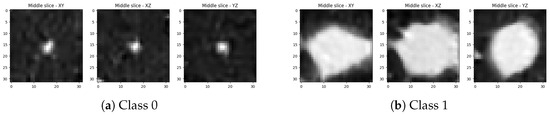

2.1. Dataset